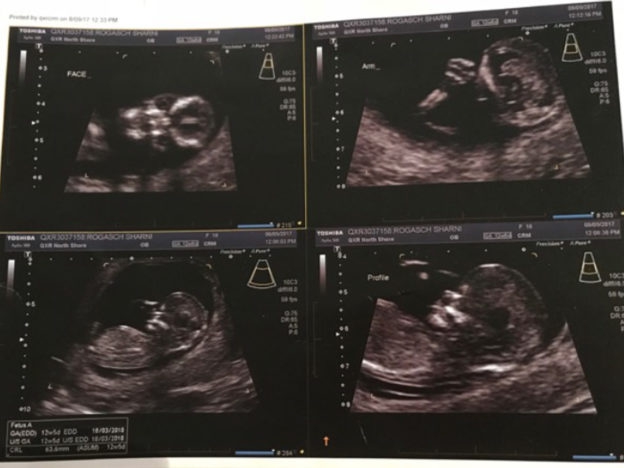

31/10/2017 17:59Mẹ trẻ Úc vừa chia sẻ ảnh siêu âm, cư dân mạng liền hốt hoảng gọi đứa trẻ trong bụng cô là “ác quỷ”

Sharni Turner, một bà mẹ trẻ tuổi người Úc vừa qua đã hạnh phúc chia sẻ bức ảnh siêu âm con lên trang Twitter của mình.

Điều đáng nói là tấm ảnh đứa bé được chụp thẳng mặt lại hiện ra giống như một chiếc đầu lâu với hố mắt đen sâu hoắm.

Nhiều bà mẹ hài hước khác cũng đã chia sẻ ảnh siêu âm quái lạ của con mình cùng với Sharni.